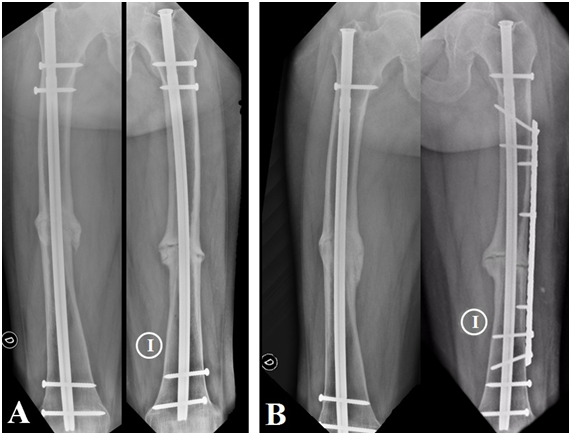

Previous to the accident the patient reported pain in both thighs of 2 months of evolution, more in the right femur, according to the patient's report the pain had been progressive and increasing with the passage of days. She was being treated at another institution where she underwent radiography, magnetic resonance imaging (MRI) and total body scintigraphy (Figure 1). Both radiographs and MRI prior to trauma showed the presence of FFA and the scintigram reported increased bilateral uptake in femur diaphysis.

Figure 1 Preliminary studies of fractures. A) X-ray B) X-ray.